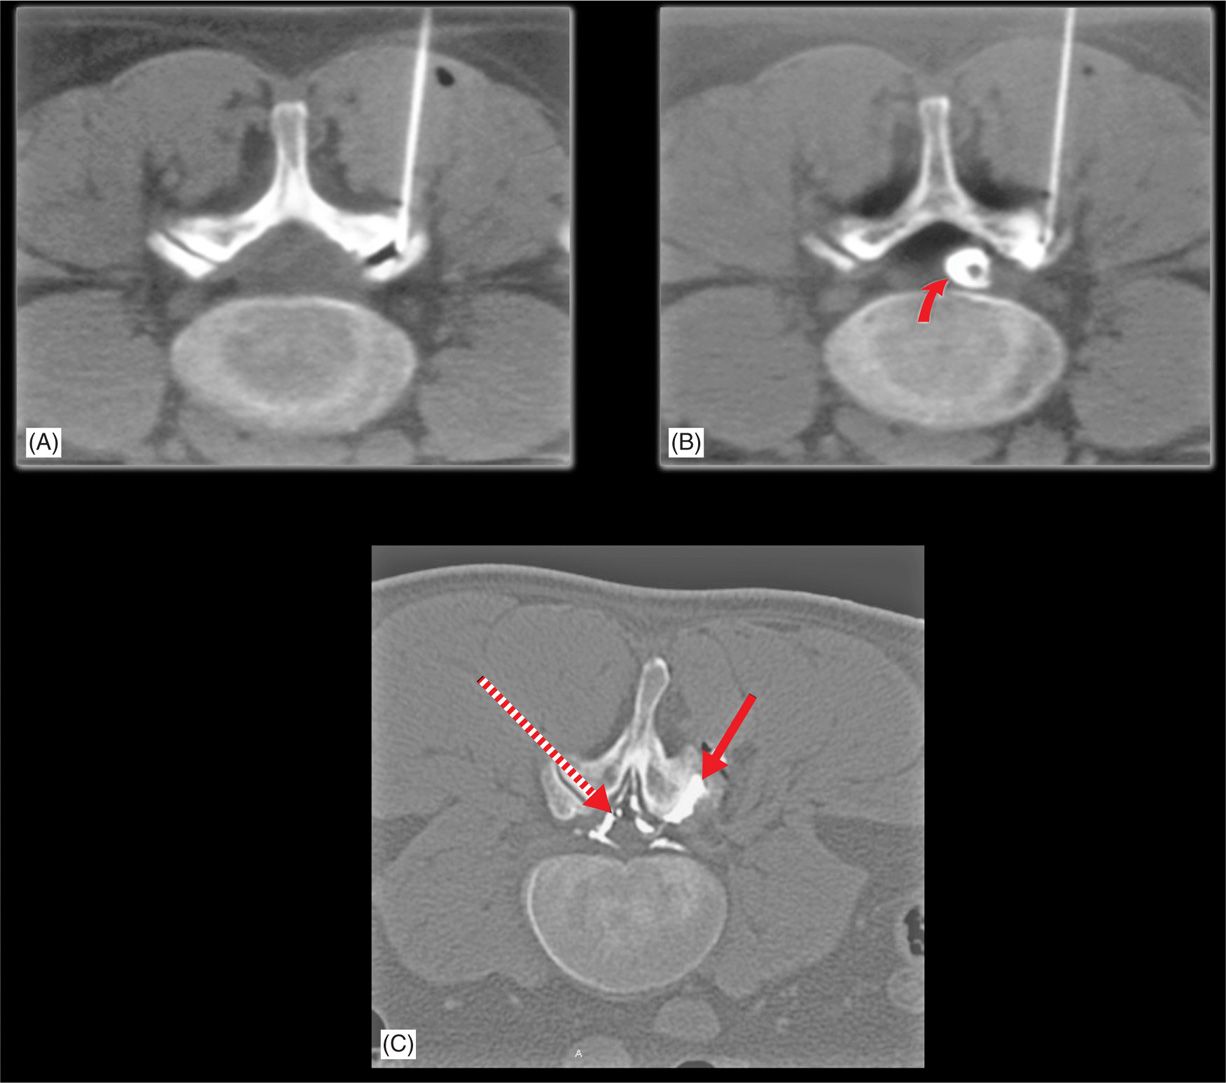

From aneskey.com

Lumbar Facet Joint Cyst Drainage and Injection Anesthesia Key Facet Joint Ganglion Cyst Mri Synovial facet cysts are degenerative lesions of the lumbar spine that can lead to lumbar spinal stenosis and cause low back pain and radicular symptoms. There is a synovial cyst associated anterior aspect of the right facet joint measuring 10 x 6 by 10 mm. On imaging, ganglion cysts can be. This contacts the posterior aspect of the exiting right. Facet Joint Ganglion Cyst Mri.

Lumbar Facet Joint Cyst Drainage and Injection Anesthesia Key Facet Joint Ganglion Cyst Mri The great majority of scs arising from facet joints occur in the lumbar spine, l4/l5 being the most affected level. The great majority of scs arising from facet joints occur in the lumbar spine, l4/l5 being the most affected level. This contacts the posterior aspect of the exiting right l5 nerve root and causes. On imaging, ganglion cysts can be.. Facet Joint Ganglion Cyst Mri.

Lumbar Facet Joint Cyst Drainage and Injection Anesthesia Key Facet Joint Ganglion Cyst Mri Synovial facet cysts are degenerative lesions of the lumbar spine that can lead to lumbar spinal stenosis and cause low back pain and radicular symptoms. On imaging, ganglion cysts can be. The great majority of scs arising from facet joints occur in the lumbar spine, l4/l5 being the most affected level. The most frequent cause of pain in facet joints. Facet Joint Ganglion Cyst Mri.

Lumbar Facet Joint Cyst Drainage and Injection Anesthesia Key Facet Joint Ganglion Cyst Mri The great majority of scs arising from facet joints occur in the lumbar spine, l4/l5 being the most affected level. The most frequent cause of pain in facet joints is osteoarthritis, which can be assessed at radiography, ct, or. This contacts the posterior aspect of the exiting right l5 nerve root and causes. On imaging, ganglion cysts can be. The. Facet Joint Ganglion Cyst Mri.